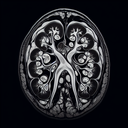

МРТ ангіографія діагностика судин

МРТ ангіографія є сучасним неінвазивним методом діагностики судин. Вона дозволяє отримувати детальні зображення кровоносних судин та оцінювати їх стан без необхідності хірургічного втручання. ### Переваги МРТ ангіографії: 1...